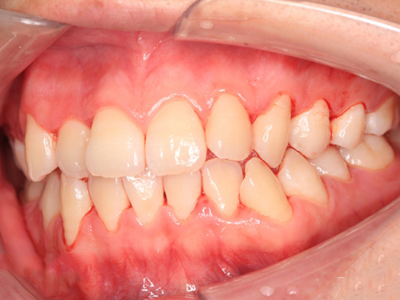

慢性龈炎又称边缘性龈炎或单纯性龈炎,主要表现为游离龈和龈乳头因炎性水肿,而变为鲜红或暗红色,龈缘变厚,龈乳头圆钝肥大。慢性龈炎的患病率高,治愈后仍可复发,部分患者可发展成为牙周炎。

慢性龈炎的病损部位一般局限于游离龈和龈乳头,以前牙区为主,尤其以下前牙区最为显著,患者常因刷牙或咬硬物时牙龈出血而就诊。游离龈和龈乳头颜色变为鲜红或暗红色,病变较重时炎性充血可波及附着龈。龈缘变厚,龈乳头圆钝肥大,可增生呈球状,覆盖牙面。牙龈松软脆弱,缺乏弹性。

当牙龈以增生性反应为主时,龈缘和龈乳头呈坚韧的实质性肥大,质地较硬而有弹性。龈沟液量增多,还可能出现龈沟溢脓现象。